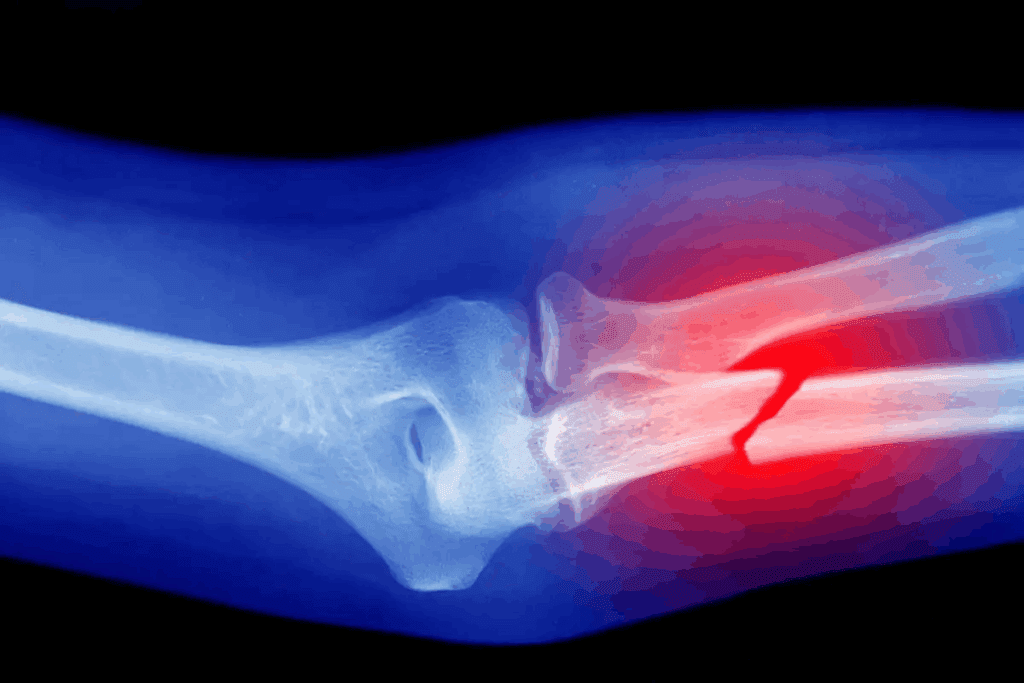

Elbow Bone Dislocations

Understanding elbow bone dislocations is key for diagnosis and treatment. They can range from mild to severe. The elbow joint, a complex hinge joint, is prone to different types of dislocations.

Dislocated Radius and Ulna

The radius and ulna bones form the elbow joint. A dislocation happens when these bones are pushed out of place. This can result from a fall or a direct hit to the elbow.

Symptoms include severe pain, swelling, and difficulty moving the elbow. Treatment involves immediate medical care to fix the dislocation and keep the joint stable. Sometimes, surgery is needed to repair damaged tissues.

Complex Elbow Dislocations

Complex elbow dislocations involve bone dislocation, fractures, or significant ligament damage. These are severe injuries needing detailed treatment, often surgery to fix the joint and repair damaged areas.